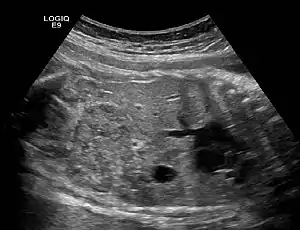

| Ectopic crossed fused kidney in a fetus approx. 34 weeks | |